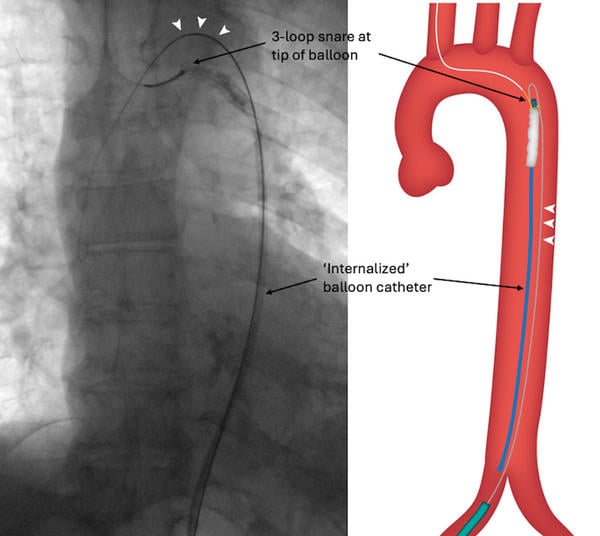

Access from the left femoral was considered, but the angulation of the iliac bifurcation was very acute. We therefore cut the balloon and Amplatzer Super StiffTM wire (Boston Scientific, Marlborough, MA, USA) 40 cm from the skin entry point, snared the very tip of the balloon catheter from the right radial artery and internalised the transected balloon system, holding the wire with forceps outside the body for maintaining access, aiming to introduce a larger sheath to help with retrieval (Figure 1C, Moving Image 1).

Figure 1C: ‘Internalisation’ of balloon with a 0.035’ wire running parallel to it (arrowheads).